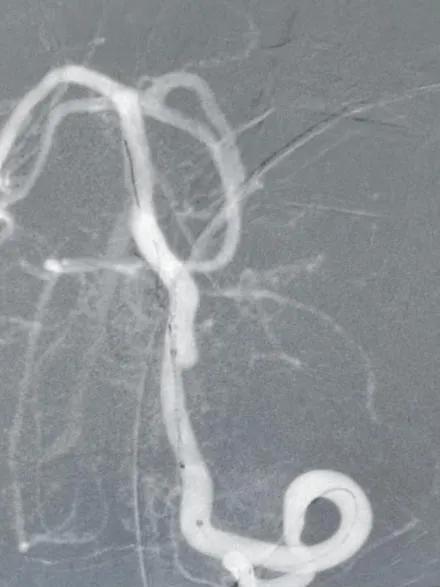

术后图像

造影显示病变部位造影剂滞留。载瘤动脉通畅,脊髓前动脉通畅。后分别行左右颈内动脉及右侧椎动脉正侧位造影,未见明显血管异常。

结束手术,患者麻醉清醒后安全返回病房,无神经功能缺失。7天后,患者康复出院。限期随访。